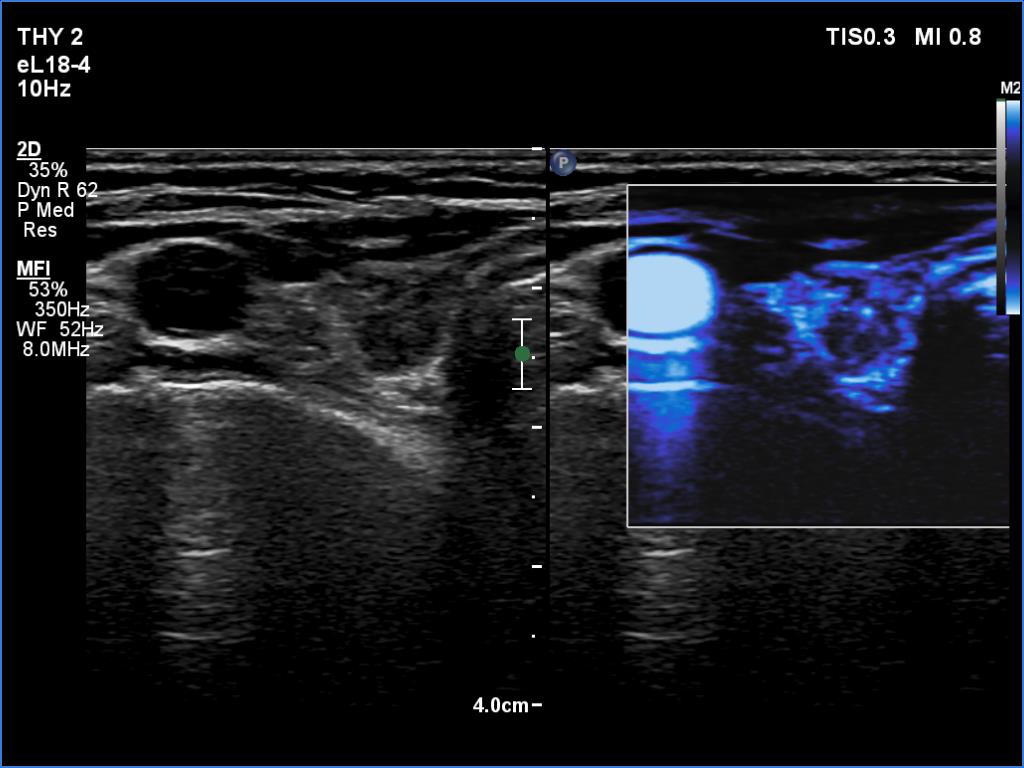

Ultrasonography. The thyroid was atrophic and hypoechoic. There was a hypoechoic mass under the lower pole of the left lobe.